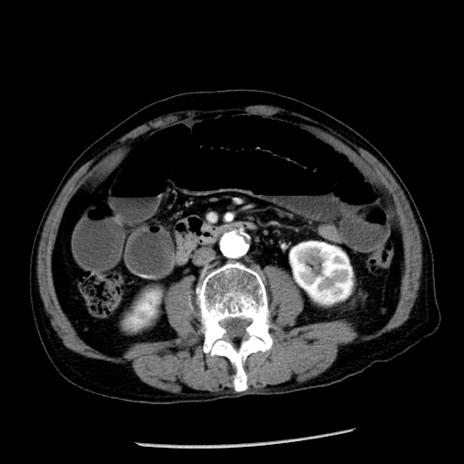

冠状断像

【症例】80歳代男性

【主訴】嘔吐

【現病歴】昨晩2回嘔吐あり、今朝になっても嘔吐あり。来院。

【既往歴】胃潰瘍

【身体所見】意識清明、BT 37.6℃、BP 166/95mmHg、HR 100bpm、SpO2 97%、腹部:平坦・軟、腸蠕動音聴取良好、圧痛なし。

【データ】WBC 21900、CRP 1.46